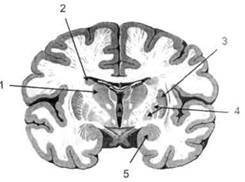

В глубине каждого полушария расположены проводящие волокна и подкорковые ядра (базальные ганглии), главные из которых — это полосатое тело (striatum), включающее в себя хвостатое ядро, скорлупу и бледный шар (pallidum). Они имеют достаточно сложную внутримозго-вую архитектуру и объединяются под общим названием — стриопал-лидарной системы (рис. 14). Эта система имеет довольно сложный филогенез, в результате которого из целостного подкоркового образования возникают упомянутые анатомические структуры, причем палли-дум из них является самым древним

Рис. 14. Основные подкорковые ядра на

вертикальном срезе больших полушарий

говного мозга:

/ — таламус; 2 — хвостатое ядро; 3 — скорлупа; 4 — бледный шар; 5 — миндалевидное тело

Рис. 19. Горизонтальный срез больших полушарий головного мозга:

/ — самая наружная капсула; 2 — наружная капсула; 3 — головка хвостатого ядра; 4 — передняя часть мозолистого тела; 5 — скорлупа; 6 — бледный шар; 7— таламус; 8 — задняя часть мозолистого тела; 9 — зрительное сияние; 10 — шпорная борозда; 11 — третий желудочек

Рис. 20. Вертикальный срез головного мозга: / — черная субстанция; 2 — зрительный тракт; 3— сильвиева борозда; 4— хвост хвостатого ядра; 5— продольная щель мозга; 6— мозолистое тело; 7— внутренняя капсула; 8 — наружная капсула; 9— таламус; 10— красное ядро; //— варолиев мост; 12— пирамиды; 13 — перекрестье пирамид